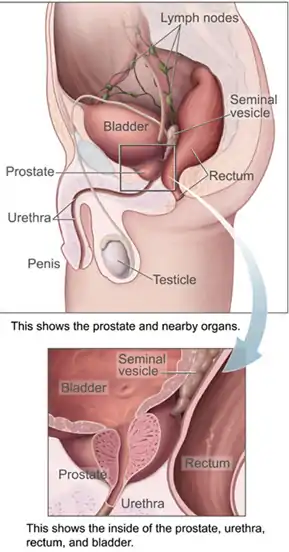

Male

In the human male, the urethra is on average 18 to 20 centimeters (7.1 to 7.9 inches) long and opens at the end of the external urethral meatus.[8]

The urethra is divided into four parts in men, named after the location:[8]

| prostatic urethra | Crosses through the prostate gland. There are several openings at the posterior wall : (1) the ejaculatory duct (2 lateral) receives sperm from the vas deferens and ejaculate fluid from the seminal vesicle, (2) prostatic sinus which has openings for several prostatic ducts where fluid from the prostate enters and contributes to the ejaculate, (3) the prostatic utricle, which is merely an indentation. These openings are collectively called the verumontanum (colliculus seminalis)

The prostatic urethra is a common site of obstruction to outflow of urine in BPH patients |

Position of the urethra in males

Position of the urethra in males Transverse section of the penis